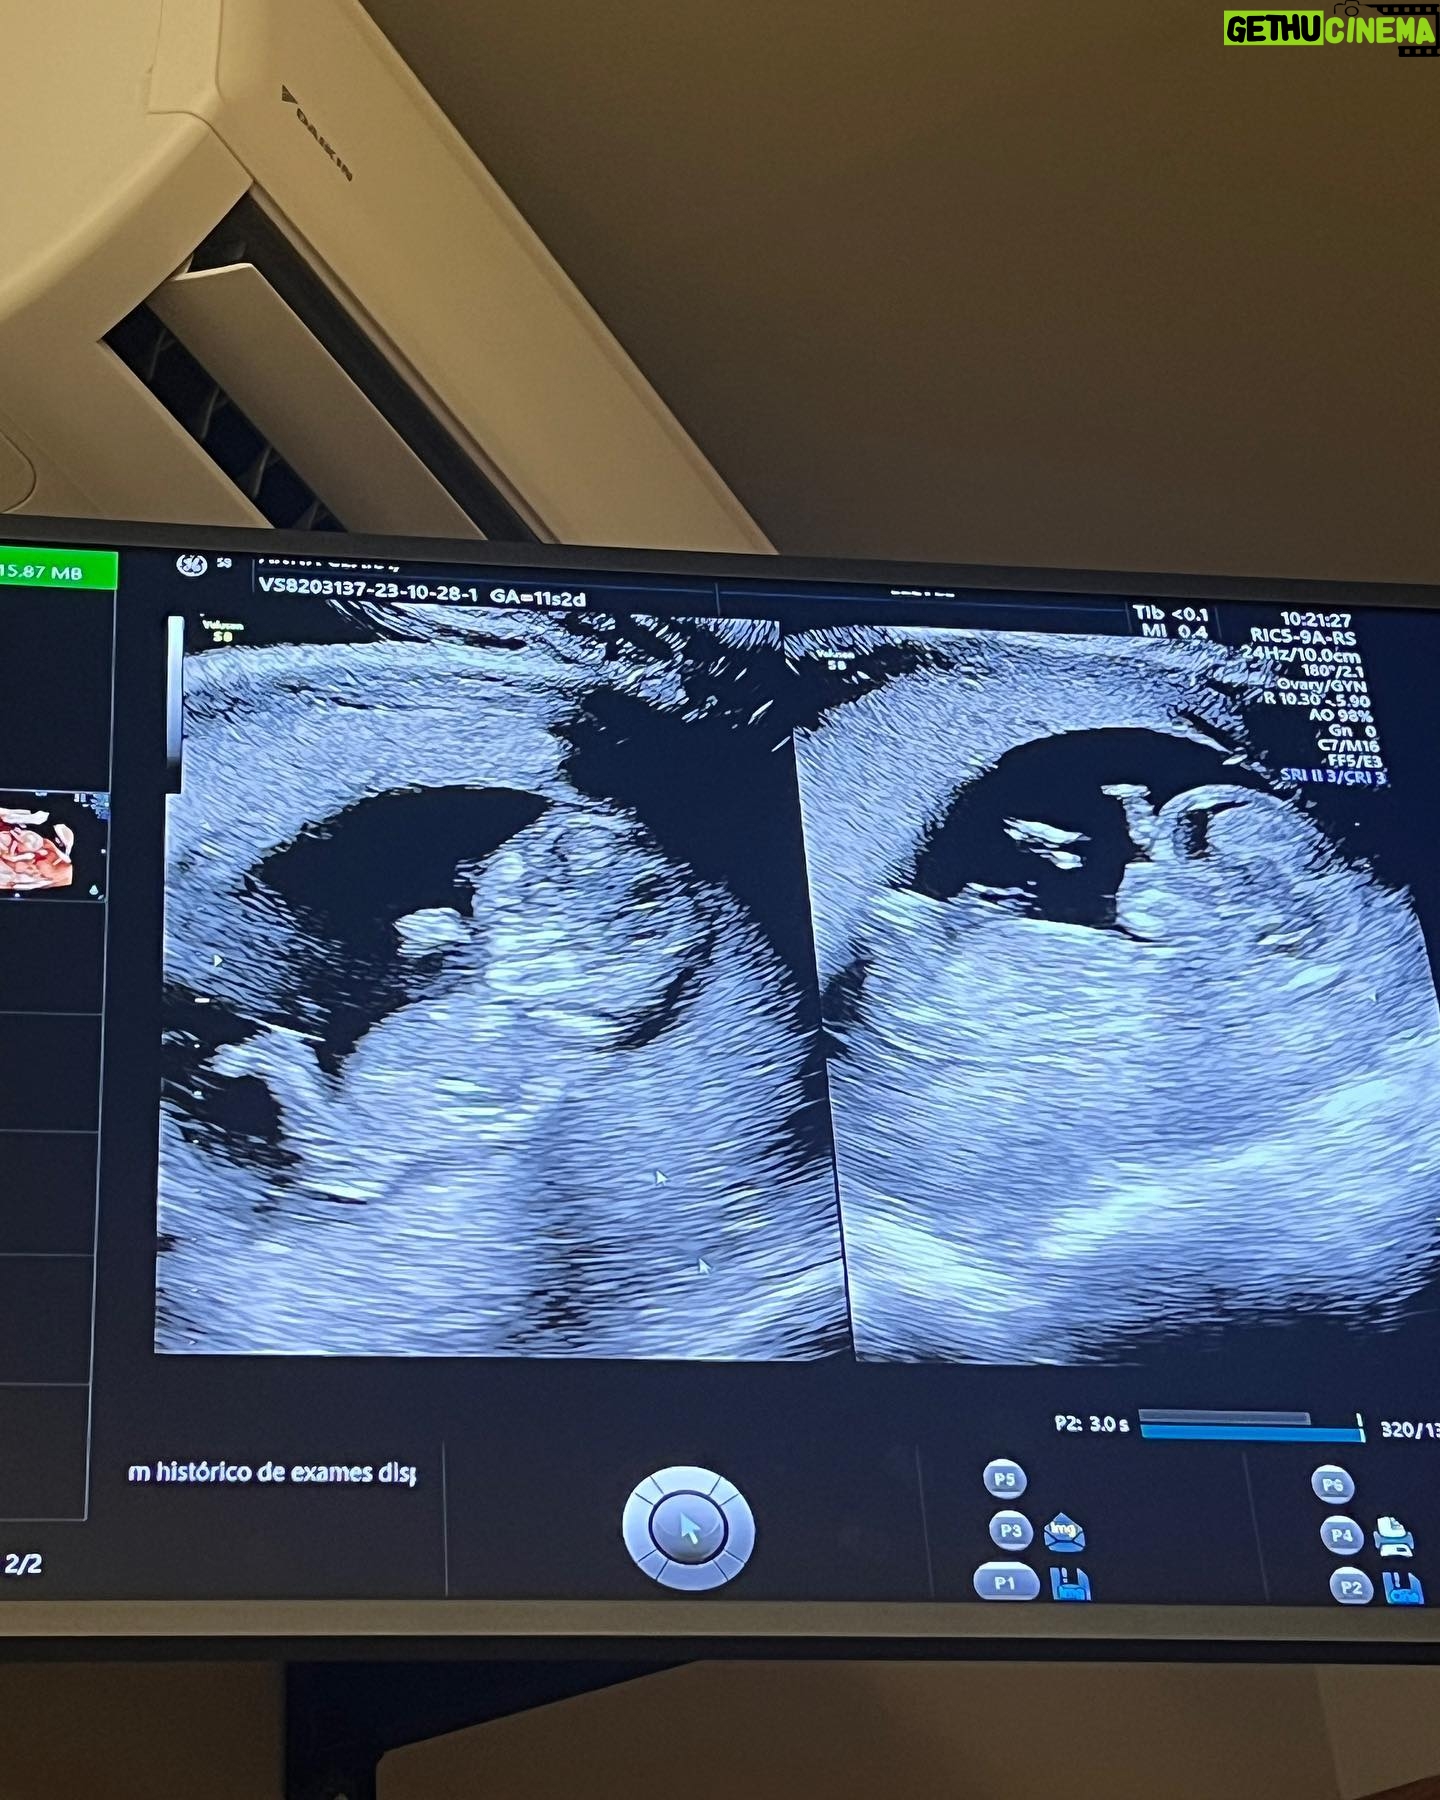

365.9K Likes – André Coelho Instagram

Caption : Mural de família das 12 semanas🤰🏻Likes : 365867

365.9K Likes – André Coelho Instagram

Caption : Mural de família das 12 semanas🤰🏻Likes : 365867

365.9K Likes – André Coelho Instagram

Caption : Mural de família das 12 semanas🤰🏻Likes : 365867

365.9K Likes – André Coelho Instagram

Caption : Mural de família das 12 semanas🤰🏻Likes : 365867

365.9K Likes – André Coelho Instagram

Caption : Mural de família das 12 semanas🤰🏻Likes : 365867

298K Likes – André Coelho Instagram

Caption : Sábado vendo as crianças 🥹🥰 e aiiiii, meninos ou meninas? 💙🩷Likes : 298035

298K Likes – André Coelho Instagram

Caption : Sábado vendo as crianças 🥹🥰 e aiiiii, meninos ou meninas? 💙🩷Likes : 298035

298K Likes – André Coelho Instagram

Caption : Sábado vendo as crianças 🥹🥰 e aiiiii, meninos ou meninas? 💙🩷Likes : 298035

298K Likes – André Coelho Instagram

Caption : Sábado vendo as crianças 🥹🥰 e aiiiii, meninos ou meninas? 💙🩷Likes : 298035

298K Likes – André Coelho Instagram

Caption : Sábado vendo as crianças 🥹🥰 e aiiiii, meninos ou meninas? 💙🩷Likes : 298035